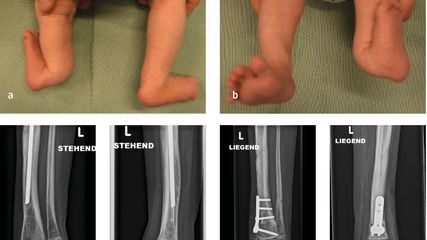

Angeborene Fehlstellungen des Unterschenkels

Kongenitale Deformitäten des Unterschenkels gehören zu den seltenen, aber medizinisch bedeutenden und operativ herausfordernden Diagnosen der Kinderorthopädie. Eine differenzierte ...